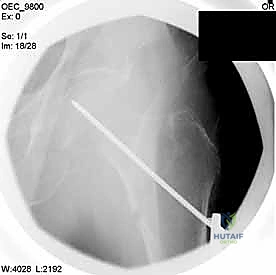

4. إدخال السلك الدليلي (Guide Wire)

يتم إدخال سلك معدني رفيع جداً عبر العظم باتجاه رأس الفخذ تحت توجيه الأشعة المستمر. هذا السلك يعمل كمسار دقيق سيتبعه المسمار النهائي. يجب أن يكون السلك في الموضع الهندسي المثالي لتجنب اختراق مفصل الورك.

مجموعة من الصور الإضافية التي توضح مراحل دقيقة من العمل الجراحي المعقد الذي يجريه الأستاذ الدكتور محمد هطيف لضمان أعلى درجات الدقة الميكانيكية الحيوية: